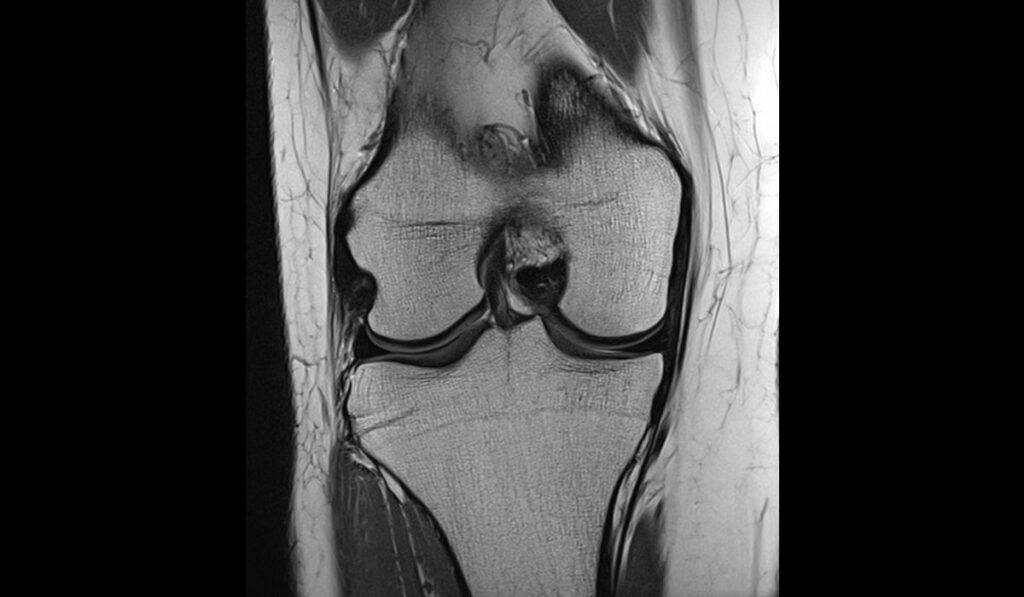

Der Innenbandriss am Knie zählt zusammen mit Verletzungen des vorderen Kreuzbands zu den häufigsten Bandverletzungen im Knie. Das Band ist dabei entweder teilweise oder komplett gerissen

Kreuzbandriss Maybach Klinik Centrum für Orthopädie Stuttgart Ein Innenbandriss im Knie ist eine häufige Verletzung, die erhebliche Schmerzen und Beschwerden verursachen kann Akute, isolierte Verletzungen von Grad I und II werden in der Regel konservativ behandelt Eine Schwellung und die Bildung eines Blutergusses im Kniegelenk sind weitere Symptome

Source: relfunpgw.pages.dev Flüssigkeit im Knie Heilpraxis , Ein Innenbandriss im Knie ist eine häufige Verletzung, die erhebliche Schmerzen und Beschwerden verursachen kann Diagnose Bei den Seitenbändern ist es zur Diagnosestellung vor allem wichtig die Aufklappbarkeit zu beurteilen.Diese muss sowohl bei gestrecktem, sowie bei 30° gebeugtem Knie beurteilt werden

Source: niciamiyl.pages.dev Wechselspiel zwischen den Pfosten , Diagnose Bei den Seitenbändern ist es zur Diagnosestellung vor allem wichtig die Aufklappbarkeit zu beurteilen.Diese muss sowohl bei gestrecktem, sowie bei 30° gebeugtem Knie beurteilt werden Der Innenbandriss am Knie zählt zusammen mit Verletzungen des vorderen Kreuzbands zu den häufigsten Bandverletzungen im Knie.